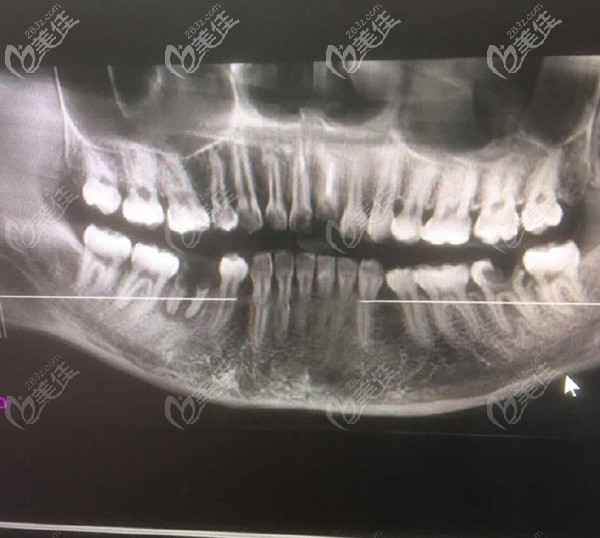

問題是本寶寶還不止缺一顆牙,只不過在我看來門牙尤為重要,來院后,醫(yī)生大概看了牙齒情況后,建議還是拍個CT看看,以便于確認給我更好的方案。

放大看看更清楚

【牙齒情況】:門牙缺失一顆,下半口缺失一顆,但是有殘根。